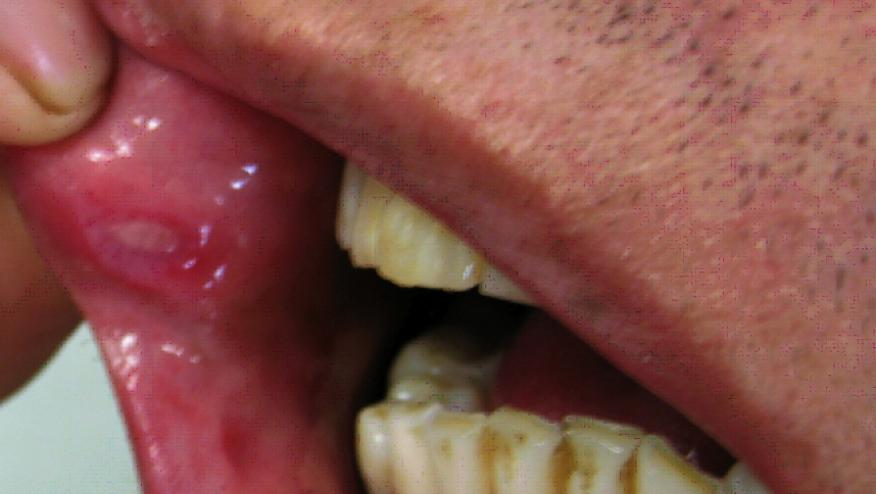

The inflammatory condition Behçet's syndrome commonly affects small blood vessels in the mouth, genitals, skin, and eyes. The highest prevalence of Behçet's occurs in northern Turkey, where it affects up to 420 in 100,000 people. This multisystem vasculitis is rarer in northern European countries and the U.S., where it generally affects fewer than one in 100,000 people. The most widespread, and often the first, symptoms of the syndrome are aphthous ulcers, which are often recurrent and may not respond to available therapies.

Note that this multisystem vasculitis generally affects fewer than one in 100,000 people in the U.S., and the most widespread symptoms of the syndrome are aphthous ulcers, which are often recurrent and may not respond to available therapies.